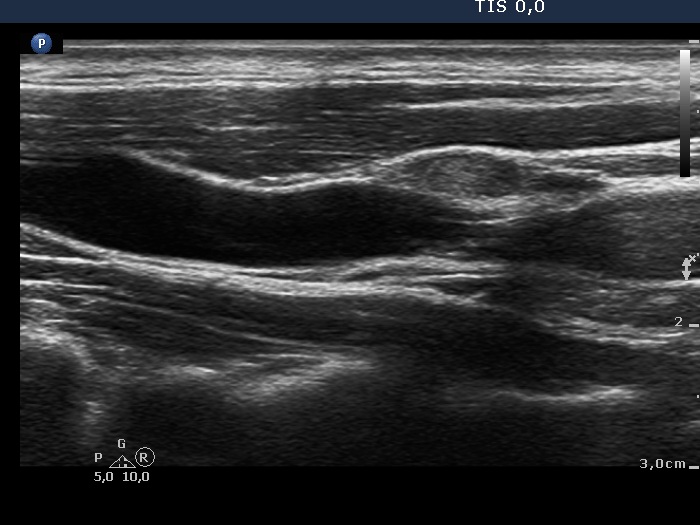

Follow-up investigation two years later (ultrasonographic picture 8)

Lateral to the left lobe, longitudinal scan. The node has echonormal or less hypoechoic and deeply hypoechoic fields.